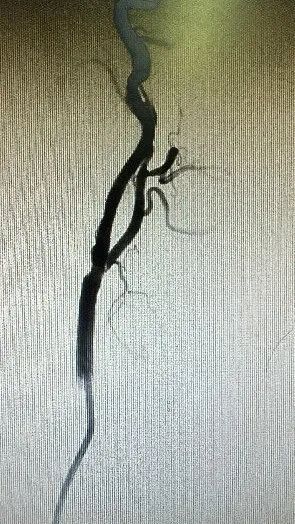

刘大爷这类患者颈动脉分叉位置高、病变斑块长,不适宜传统颈动脉内膜切除术,同时他主动脉有较多溃疡斑块,远端颈动脉扭曲,因此传统经股动脉入路颈动脉支架植入术(TFCAS)风险较大。经华山医院血管外科团队严格的术前评估后,团队决定应用TCAR技术规避CEA和TFCAS技术的不足,为刘大爷进行治疗。手术仅历时1小时便顺利完成,术后刘大爷恢复良好,脑缺血症状消失,于第三天顺利出院。

术后造影